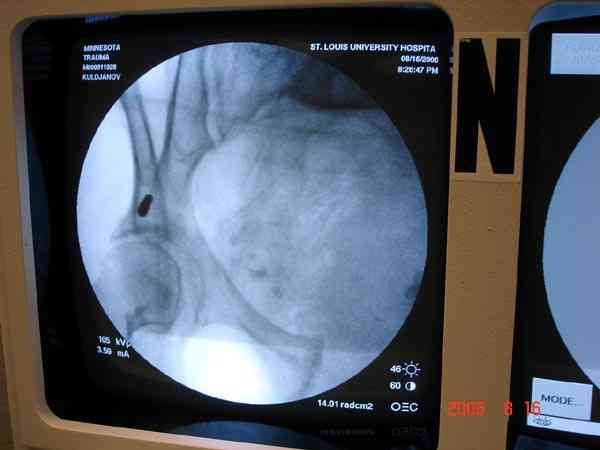

Прооперировали молодую девушку 32 лет спустя 9 мес после травмы. Имелся стойкий болевой синдром, неопороспособность левой н/конечности, моторные и сенсорные нарушения в левой голени и стопе, патологическая подвижность левой половины таза. Первым этапом закрыто в аппарате исправили деформацию ( в течении 2,5 нед). Вторым закрытое введение илиосакральных винтов в крестец (канюллированные 7,2 мм Chm) + туннелизация зоны псевдоартроза спицама Киршнера, реконструкция передних отделов таза, накостный остеосинтез . Аппарат частично демонтирпован, оставлена "передняя рама" После устранения деформации отмечен регресс неврологической симптоматики, уменьшение болевого синдрома. Интересующие вопросы: 1. Прогноз для сращения псевдоартроза крестца. 2. сроки нагрузки весом левой половины таза. Буду очень признателен за ваши мнения по этому поводу.A female 32 y.o. admitted to our unit 9 months after initial injury with pain, inability to bear weight at the left lower limb, sensor and motor disturbances in the left foot and tibia, with mobility of the left hemipelvis.At first closed reduction was performed by an external fixator within 2,5 weeks. After correction her pain decreased and some neurological progress was achieved. Now two iliosacral screws 7,2 mm were inserted, and anterior lesion was fixed by a plate. External fixator was partially unmounted, only anterior frame left in place.Images attached.How would you evaluate chances of healing of the sacrum with the current position?When would you allow weight-bearing of the left leg?THX in advance.

Примерно такой фиксатор наложил вчера ночью, но патология была экстренная травма: больному 53 года, поступил после мотоциклетной травмы, черепно-мозговой, абдоминальной, челюстно лицевой с потерей одного глаза, сосудистой и из скелета перелом крестца слева с диастазом симфиза и множественные переломы ребер.

Здесь соблюдался алгоритм больному с внутритазовым кроветечением после нестабильного перелома таза.

Одновременно с хирургами, которые занялись ксплоративной лапаротомией, мы приступили к фиксации временным аппаратом для уменьшения диастаза симфиза. После установки аппарата удалось стабилизировать давление, потом наше место занял сосудистый хирург, который нашел кровоточащую левую артерию epigastrica. Кровоточаший сосуд затромбизировал эндоваскулярно введением 4 coil placement.